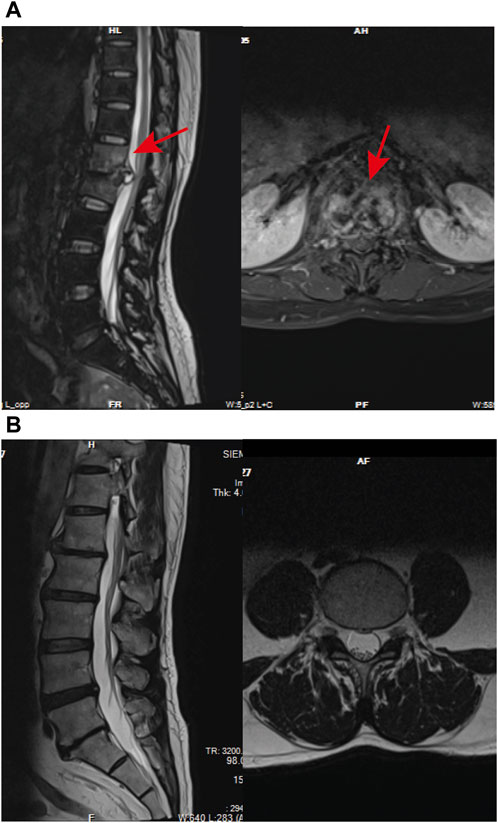

GO and kyoto encyclopedia of genes and genomes enrichment analysis for DEPsFunctional enrichment analysis demonstrated that the DEPs were primarily involved in the immune system process and response to stimulus, which might be associated with the Rifampicin-resistant mechanism of spinal tuberculosis induced by the immune system process (Figure 5A). Notably, five proteins annotated with the term human leukocyte antigen, A Chain ((HLA-A), human leukocyte antigen, C Chain ((HLA-C), HLA Class II Histocompatibility Antigen, DRB1 Beta Chain (HLA-DRB1), metalloproteinase 9 (MMP9) and Phospholipase C-like 1 (PLCL1) were significantly changed compared with NDSTB (Supplementary Table S4). KEGG pathway analysis demonstrated that DEPs were mainly associated with “Antigen processing and presentation” and “Phagosome” (Figure 5B). These findings contribute novel perspectives to our understanding of the etiology and comorbidities associated with drug-resistant spinal tuberculosis.

Figure 5. (A) BP, the cellular component category (CC), the molecular function category (MF) phantom enrich mentanalysis of DEPs. The left vertical coordinate is count (number of differential proteins annotated to the term), and the right vertical coordinate is percentage (number of differential proteins annotated to the term/total number of differential proteins with GO annotations). (B) KEGG enrichment pathway analysis of DEPs. The abscissa represents the negative logarithmic transformation of the Enrichment factor, and the ordinate represented the specific path. The column color indicates -log10 (p-value). Specific counts and p-values are presented on the right side of the column. KEGG, Kyoto Protocol Encyclopedia of Genes and Genomes; DEPs, differentially expressed proteins.

PPI analysis confirmed by Immunohistochemistry and Western blot analysisThrough KEGG signaling pathways analysis, it was revealed that HLA-DRB1, HLA-A, HLA-C, MMP9, and PLCL1 among the 25 DEPs were linked to “Antigen processing and presentation” and “Phagosome” pathways (as depicted in Figure 6A). To further exprole, results revealed that the expression of MMP9 and PLCL1 were remarkably decreased in the focal tissues of DSTB, compared with NDSTB. Contrarily, the HLA-A, HLA-C, and HLA-DRB1 were significantly increased in the focal tissues of DSTB, compared with NDSTB (Figures 6B,C), suggesting that five proteins (HLA-DRB1, HLA-A, HLA-C, MMP9 and PLCL1) may be involved in Rifampicin-resistant STB.

Figure 6. (A) “DEPs-drug-resistant spinal TB- “Antigen processing and presentation “pathway -“Phagosome” pathway -DEPs-Targets” network. Protein-protein interaction network using STRING. A PPI of all detected DEPs. The significantly enriched pathways (p < 0.05) and protein/protein coding gene and protein-protein interaction network associated with the pathways. The innermost circle is 5 of the key proteins of DEPs. The darker the color, the greater the degree value. The criteria for sub-setting was the more and denser the edges, the more central the protein was. The innermost five key proteins in the circle are most relevant to these two pathways. These proteins are particularly relevant to the mentioned pathways, with green highlighting their involvement in “Antigen processing and presentation” and “Phagosome.” (B) Relative expression of MMP9, PLCL1, HLA-A, HLA-C and HLA-DRB1 measured using the tissue protein of DSTB and NDSTB were tested by Western blot (n = 5). Statistically significant differences between groups were determined using a Student’s t-test or two-tailed one-way analysis of variance, followed by a Student-Newman-Keuls test; *p < 0.05. (C) IHC staining of tissue in the focal tissues of DSTB (n = 20) and NDSTB (n = 20) for MMP9, PLCL1, HLA-A, HLA-C and HLA-DRB1. scale bars = 200 µm.

Pharmaco-transcriptomic analysisBased on the above results, HLA-A, HLA-C, HLA-DRB1, MMP9 and PLCL1 may be potential therapeutic targets for DSTB. Therefore, the results of our pharmaco-transcriptomic analysis can confirm that 13 drug compounds (e.g., Floxacillin, Clavulanic, and Amoxicillin) can regulate the expression of HLA-C. Similarly, there were 12 kinds of drug compounds found regulating MMP9, such as Celecoxib, Marimastat, and Andecaliximab. Moreover, 15 kinds of drug compounds (Terbinafine, Zonisamide, Ticlopidine, etc.) regulated the expression of HLA-A. In addition, Flupirtine, Fluvastatin, Methimazole, and other 18 drug compounds were confirmed to regulate the HLA-DRB1 (Figure 7). These experimental results will help us provide new insights into the treatment of DSTB.

Figure 7. We performed pharmaco-transcriptomics analysis by the results of key proteins for the PPI network.pharmaco-transcriptomic analysis used the Integration of the Drug–Gene Interaction Database (DGIdb 4.0).

DiscussionIn this study, TMT labeled Quantitative Proteomicswas employed to scrutinize the protein expression profiles of focal tissues in DSTB patients as compared to NDSTB. The identified signaling pathways, specifically “Antigen processing and presentation” and “Phagosome,” linked to DSTB, shed light on potential mechanisms underlying Rifampicin-resistance. Furthermore, five proteins (HLA-DRB1, HLA-A, HLA-C, MMP9 and PLCL1) were identified to be potential targets for DSTB.

It is worth noting that drug resistance of patients with spinal TB underlines at a higher rate under clinical use of four first-line drug combinations than theoretically predicted (Gao et al., 2016). Nahid et al. highlighted the choice and number of drugs significantly impact the speed of drug resistance spread, and exproled the mechanism of drug-resistant STB was extremely urgent (Nahid et al., 2019). Notably, our screening process identified five key proteins, HLA-DRB1, HLA-A, HLA-C, MMP9, and PLCL1, with distinct upregulation or downregulation in Rifampicin-resistant STB patients. Recent research has demonstrated that the HLA class II presentation of Mycobacterium bacterial antigens to CD4+ cells is one of the most crucial biological steps regarding the outcome of the infection (Magira et al., 2012), CD8 T lymphocytes recognize bacteria exposed at the membrane of infected cells. In addition, our study revealed the involvement of HLA-DRB1, HLA-A, HLA-C in the signaling pathways of antigen processing and presentation, suggesting their potential as targets by CD4+ for STB Rifampicin-resistance. MMP9 was reported closely involved in immune inflammation. Several cell types, including epithelial cells, macrophages, fibroblasts, and neutrophils, produce pro-MMP9 (Van den Steen et al., 2002). Therefore, MMP9-inhibiting monocytes can suppress the invasion of T lymphocytes into the walls of blood vessels, causing decreasing the density of an immune response that leads to vasculitis (Watanabe et al., 2018). These results indicate that HLA-DRB1, HLA-A, HLA-C, MMP9, and PLCL1 may play pivotal roles in the mechanism of Rifampicin-resistant spinal TB, potentially serving as diagnostic markers and promising therapeutic targets for DSTB.

Interestingly, HLA-DRB1, HLA-A and HLA-C were significantly increased in DSTB group, but MMP9 and PLCL1 were substantially decreased in DSTB group. The pharmaco-transcriptomic analysis identified various drugs (Floxacillin, Clavulanic, Ustekinumab and so on) capable of regulating the expression of these proteins. Ustekinumab, a human monoclonal antibody, was kown as a target inhibition of interleukin-12 and −23. Moreover, Morelli et al., 2022 demonstrated that interleukin-12/23 was related to HLA-C, since they preferentially present (auto) antigens, for example the metalloprotease (MMP) domain, to CD8 T cells. Our paper demonstrated that Ustekinumab could regulate the protein of HLA-C, which might be one of the mechanisms of Ustekinumab-induced upregulated risk of Rifampicin-resistant of spinal TB disease.